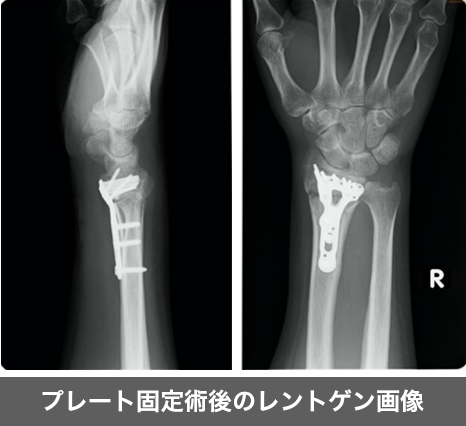

橈骨遠位端骨折は転倒した際に手をついて受傷しやすい骨折で骨折しやすい4大骨折の一つです。

骨粗しょう症の方など骨密度が低い方は軽く手をついた場合にも起こる事もあります。

主な治療方法として骨折部位に転位(ずれ)が生じていなければギプスによる固定を行い、転位が生じているようであれば手術により転位を元の位置に戻して金属プレートによる固定を行います。

近年は固定材料が改良されてきており、術後早期のリハビリテーションが可能となってきております。